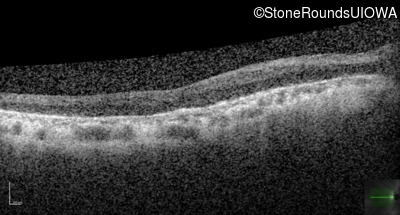

Optical Coherence Tomography - Left - 20/70 +1

Exemplar / OCT Stack